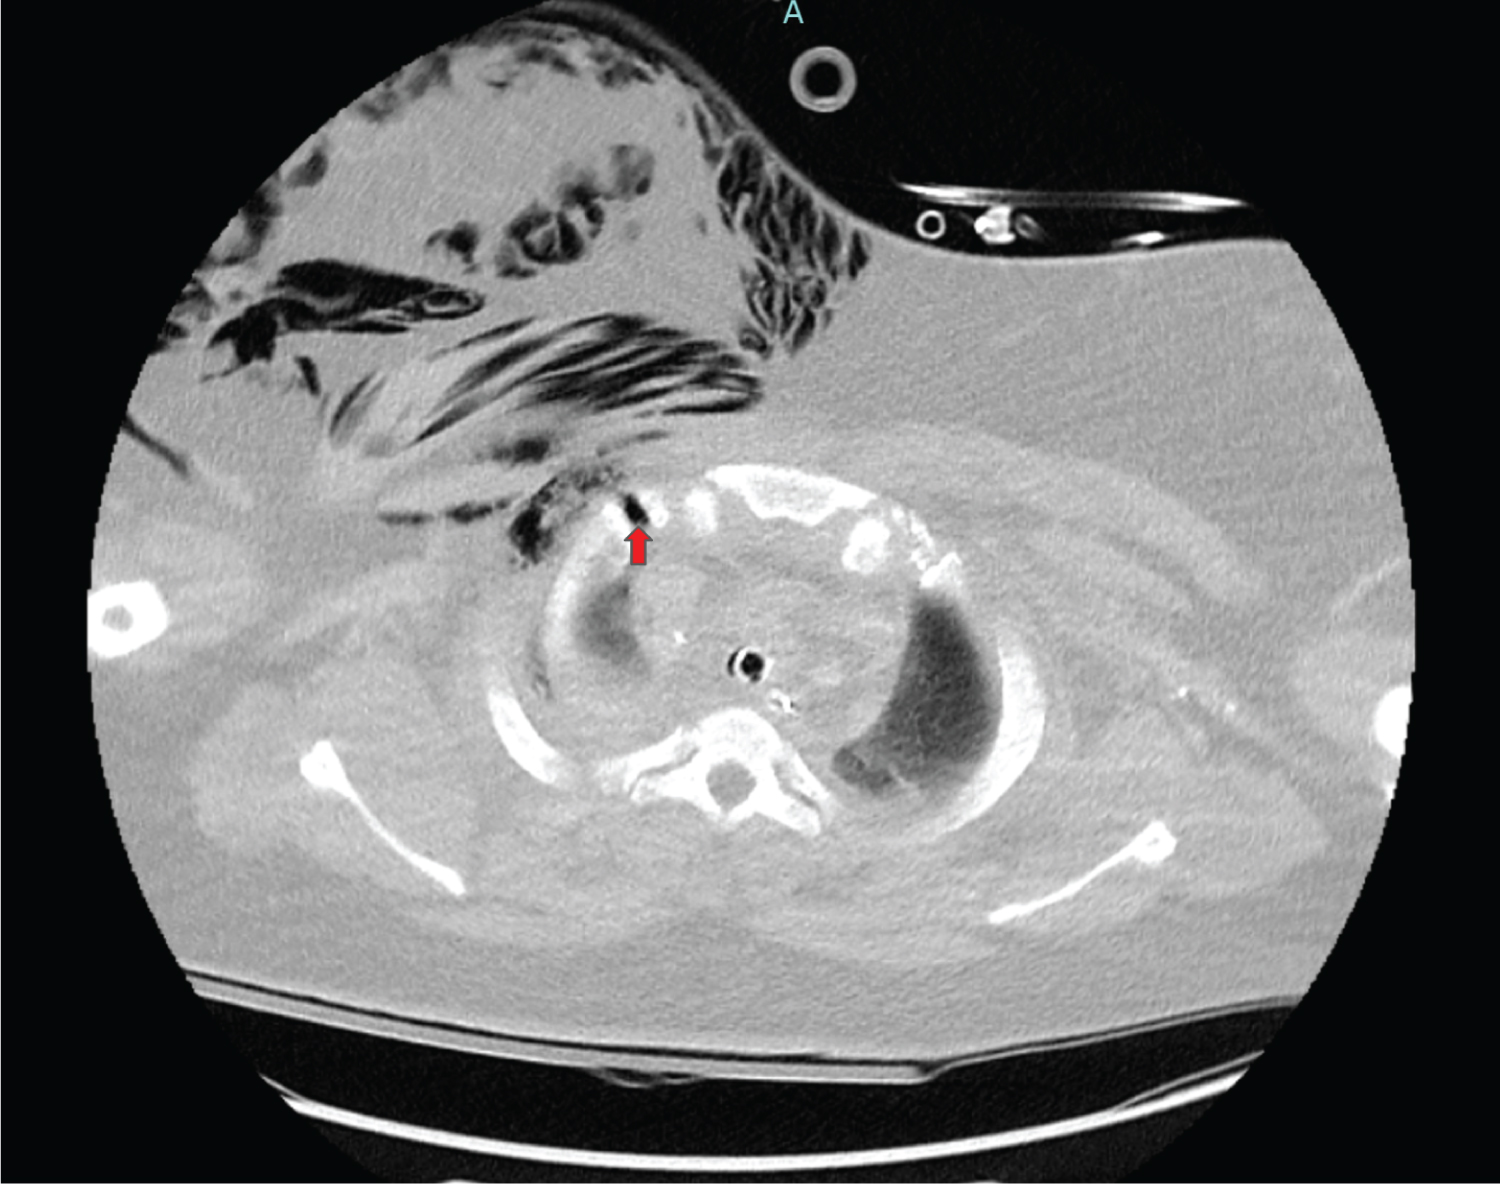

X-Ray eight hours later showed subcutaneous emphysema of the right chest wall (Figure 2A), with corresponding computed tomography (CT) showing worsening of the right-sided pneumothorax, as well as an intercostal pleurocutaneous fistula along the anterior superior chest wall (Figure 2B). A right-sided chest tube was then placed, and daily X-rays were performed to assess for resolution of the fistula (Figure 3). Within 12 hours improvement was seen, and within 36 hours the subcutaneous emphysema was nearly resolved (Figure 4).

Figure 2b: Axial CT with contrast shows the right-sided pleurocutaneous fistula (red arrow) with resulting subcutaneous emphysema of the right chest.